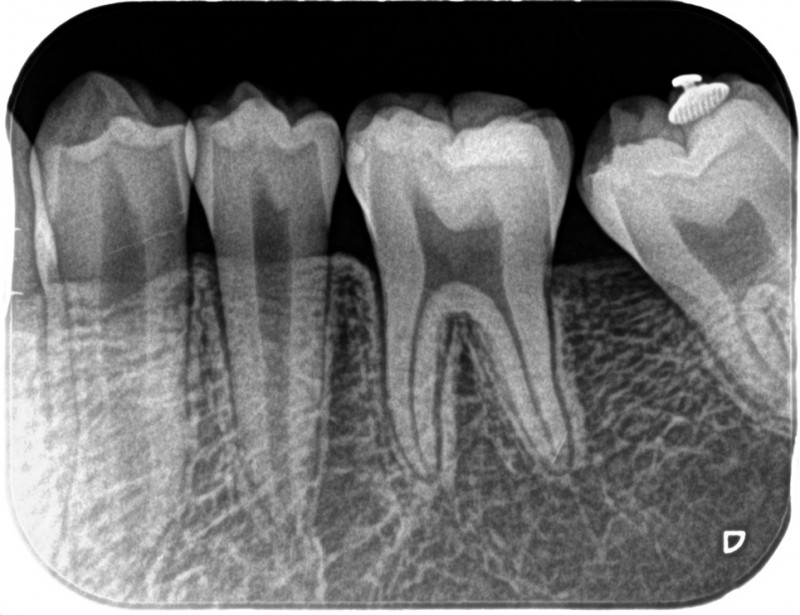

↑半年で起きました。

このケース、早期に治療を開始したことと、真面目に患者さんが装置を入れてくれたことにより、簡単に改善することができました。